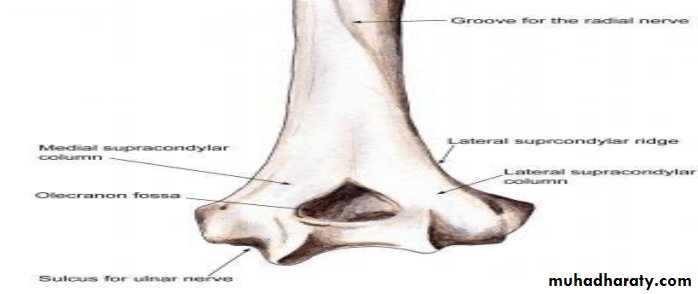

Anatomy

The distal humerus anatomy is especially predisposed to injury because its configuration in two columns connected by thin bone represents a zone of weakness.When a fall on the outstretched hand occurs, the olecranon engages on the olecranon fossa and if elbow extension progresses, the olecranon finally acts as a fulcrum on the fossa. Therefore, the bone begins to break at first anteriorly and the fracture progresses posteriorly